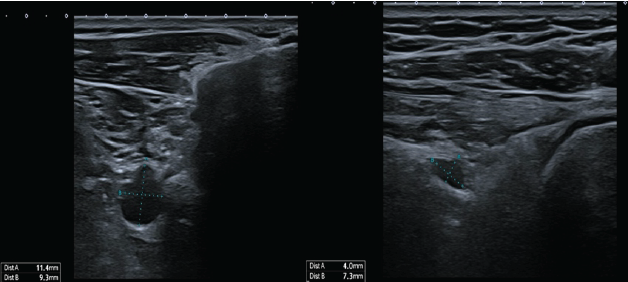

A 63-year-old right-handed woman with no relevant medical history presented with a 6-month history of continuous dull right shoulder pain, aggravated by lying on the affected side and associated with nocturnal pain. She reported functional limitations in overhead activities. Analgesics included paracetamol, ibuprofen, and topical diclofenac. Her regular physical activities included walking and cycling. Examination showed normal biceps and triceps reflexes, intact sensation, negative Spurling’s test, and preserved cervical and cervicodorsal mobility with negative facet joint and foraminal compression tests. Increased tone was noted in the postural muscles, mainly in the upper trapezius. Shoulder assessment revealed painless passive external rotation and abduction-external rotation, but active external rotation strength was reduced to 4/5 on the Medical Research Council scale. Impingement signs and Jobe’s test were negative. Palpation over the suprascapular notch elicited tenderness. Ultrasound revealed a cystic lesion posterior to the glenoid. Arthro-MRI confirmed a cyst from the spinoglenoid to the suprascapular notch along the course of the SSN. No teres minor atrophy was observed. Additional findings included insertional tendinopathy of the supraspinatus and a superoposterior labral tear. The imaging appearance was consistent with an intraneural ganglion cyst. Electromyography (EMG) showed a right SSN lesion at or proximal to the supraspinatus muscle branch, consistent with a partial axonotmesis and associated with moderate-to-severe muscular involvement. The patient initially opted for a conservative approach with physiotherapy, ultrasound-guided aspiration, and intralesional glucocorticoid injection for symptomatic relief (Depo-Medrol 80 mg). Aspiration of the cyst was attempted. However, only 1 mL of the thick mucinous fluid could be retrieved. At 4 weeks, pain improved but there was persistent fatigue with overhead activity and weakness in both the supraspinatus and infraspinatus. Ultrasound showed a persistent anechoic, lobulated cyst (9.4 × 7.6 mm) in the suprascapular notch, with extension to the spinoglenoid (4.1 × 7.4 mm) notch, without hyperemia. Physiotherapy was continued, with follow-up planned in 2 months. Two months later, ultrasound showed enlargement at the suprascapular notch (11.4 × 9.3 mm) and a stable size at the spinoglenoid notch (4.0 × 7.3 mm) (Fig. 2). EMG revealed improved compound muscle action potential (CMAP) amplitude and recruitment in the supraspinatus, but decreased recruitment and denervation in the infraspinatus. A surgical indication was made for arthroscopic decompression of the cyst at both the suprascapular and spinoglenoid notches and treatment of the labral tear. Arthroscopy revealed a degenerative type IIB superior labrum anterior to posterior (SLAP) lesion, treated with biceps tenotomy and labral debridement, as repair was deemed infeasible. Cyst decompression exposed a well-defined synovial cyst wall surrounding the nerve. Incision released a wine-red mucinous fluid, and the wall was carefully debrided to achieve complete decompression (Fig. 1)

Figure 2: Ultrasound imaging of the right shoulder 3 months after cyst aspiration and intralesional glucocorticoid injection. The cyst shows enlargement at the suprascapular notch (11.4 × 9.3 mm), with a stable size at the spinoglenoid notch (4.0 × 7.3 mm).